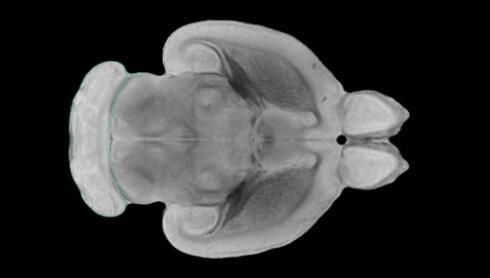

隨著機體年齡增加,肌肉和關(guān)節(jié)都會變得僵硬,這就會使得日?;顒幼兊酶永щy,本文研究表明,我們的大腦也是如此,與年齡相關(guān)的大腦僵硬對大腦干細胞的功能或許有著重要影響。文章中,研究人員對年輕和老化大鼠的大腦進行研究闡明了年齡相關(guān)大腦僵硬對少突膠質(zhì)前體細胞(OPCs,oligodendrocyte progenitor cells)功能的影響。OPCs是一類對維持正常大腦功能非常重要的大腦干細胞,其對于髓磷脂的再生也非常重要,髓磷脂是神經(jīng)組織周圍的脂肪鞘,在多發(fā)性硬化癥中髓磷脂的再生常常會被損傷,機體老化對這些細胞的影響常常會誘發(fā)多發(fā)性硬化癥的發(fā)生,這些細胞的功能在老化的健康人群中同樣會下降。

為了確定老化OPCs的功能缺失是否可以被逆轉(zhuǎn),研究人員將來自老化大鼠機體的老化OPCs轉(zhuǎn)移到了年輕大鼠柔軟的海綿狀大腦組織中去,值得注意的是,這些老化的大腦細胞能夠重新恢復(fù)活力,其行為非常像年輕更加強壯的細胞。這項研究中,研究人員在實驗室中開發(fā)出了具有可變僵硬程度的新型材料,并在受控環(huán)境下研究這些材料的生長及其對大鼠大腦干細胞的影響,這些材料能被工程化改造具有和年齡或老化大腦相似的柔軟程度。

為了深入理解大腦組織柔軟和僵硬影響細胞行為的分子機制,研究人員對細胞表面一種名為Piezo1的蛋白質(zhì)進行了分析,該蛋白質(zhì)能“告知”細胞其周圍的環(huán)境為柔軟或僵硬。研究者Kevin Chalut說道,我們發(fā)現(xiàn),當(dāng)在僵硬材料上促進年輕具有功能性的大鼠干細胞時,這些細胞就會表現(xiàn)出功能異常,并失去其再生的能力,實際上其行為與老化細胞相似。當(dāng)將老化的大腦細胞在柔軟材料上生長時,其功能就會表現(xiàn)得像年輕細胞一樣,換句話說,其能夠重新恢復(fù)年輕的活力。